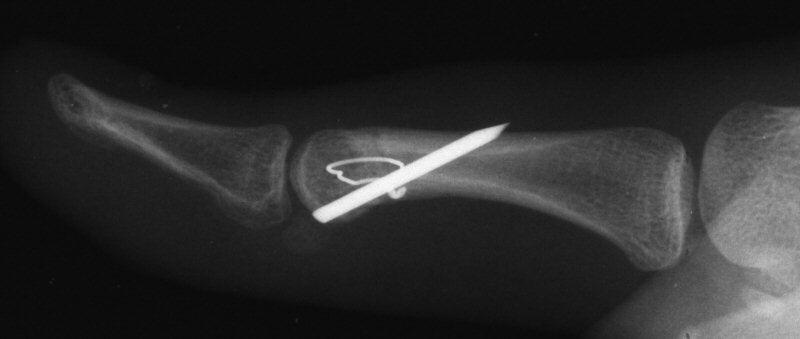

Case 3. 21 year old woman with pain developing in a congenitally angulated thumb.

Radiographs show a juxtaarticular ossification with  subchondral cyst formation of the bone interface with the lateral phalangeal head and lateral angulation of the proximal phalanx articular surface.